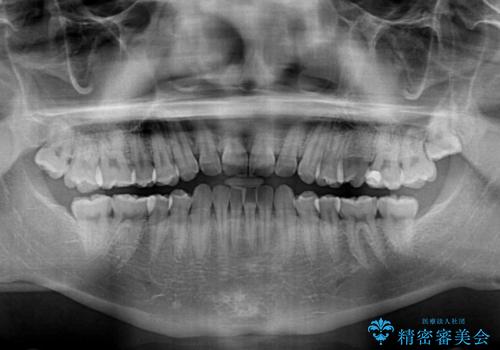

・上顎左右の第二大臼歯が頬側へ転移し、シザーズバイト(scissors bite)の状態

・上顎左側第二小臼歯が90度捻転しており、噛み合わせに影響

・奥歯のシザーズバイト改善には、口蓋側にアンカースクリュー(TAD)を設置し、矯正用ゴムで内側に牽引

・捻転した第二小臼歯は、ワイヤーと矯正用ゴムの力を用いて正しい位置へ回転移動